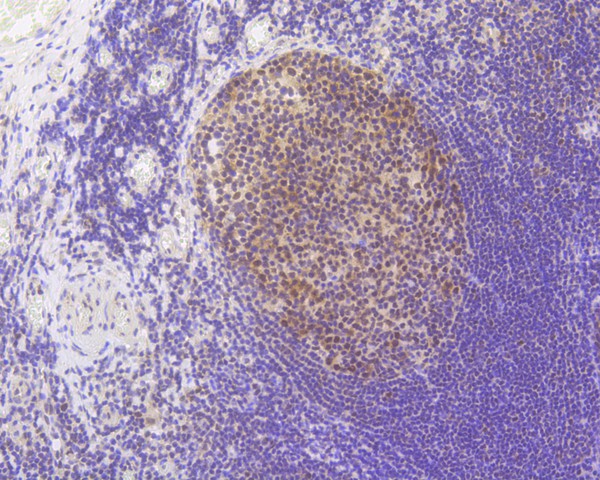

Immunohistochemical analysis of paraffin-embedded human tonsil tissue using anti-MLH1 antibody. The section was pre-treated using heat mediated antigen retrieval with Tris-EDTA buffer (pH 8.0-8.4) for 20 minutes.The tissues were blocked in 5% BSA for 30 minutes at room temperature, washed with ddH2O and PBS, and then probed with the primary antibody (HA750077, 1/200) for 30 minutes at room temperature. The detection was performed using an HRP conjugated compact polymer system. DAB was used as the chromogen. Tissues were counterstained with hematoxylin and mounted with DPX.